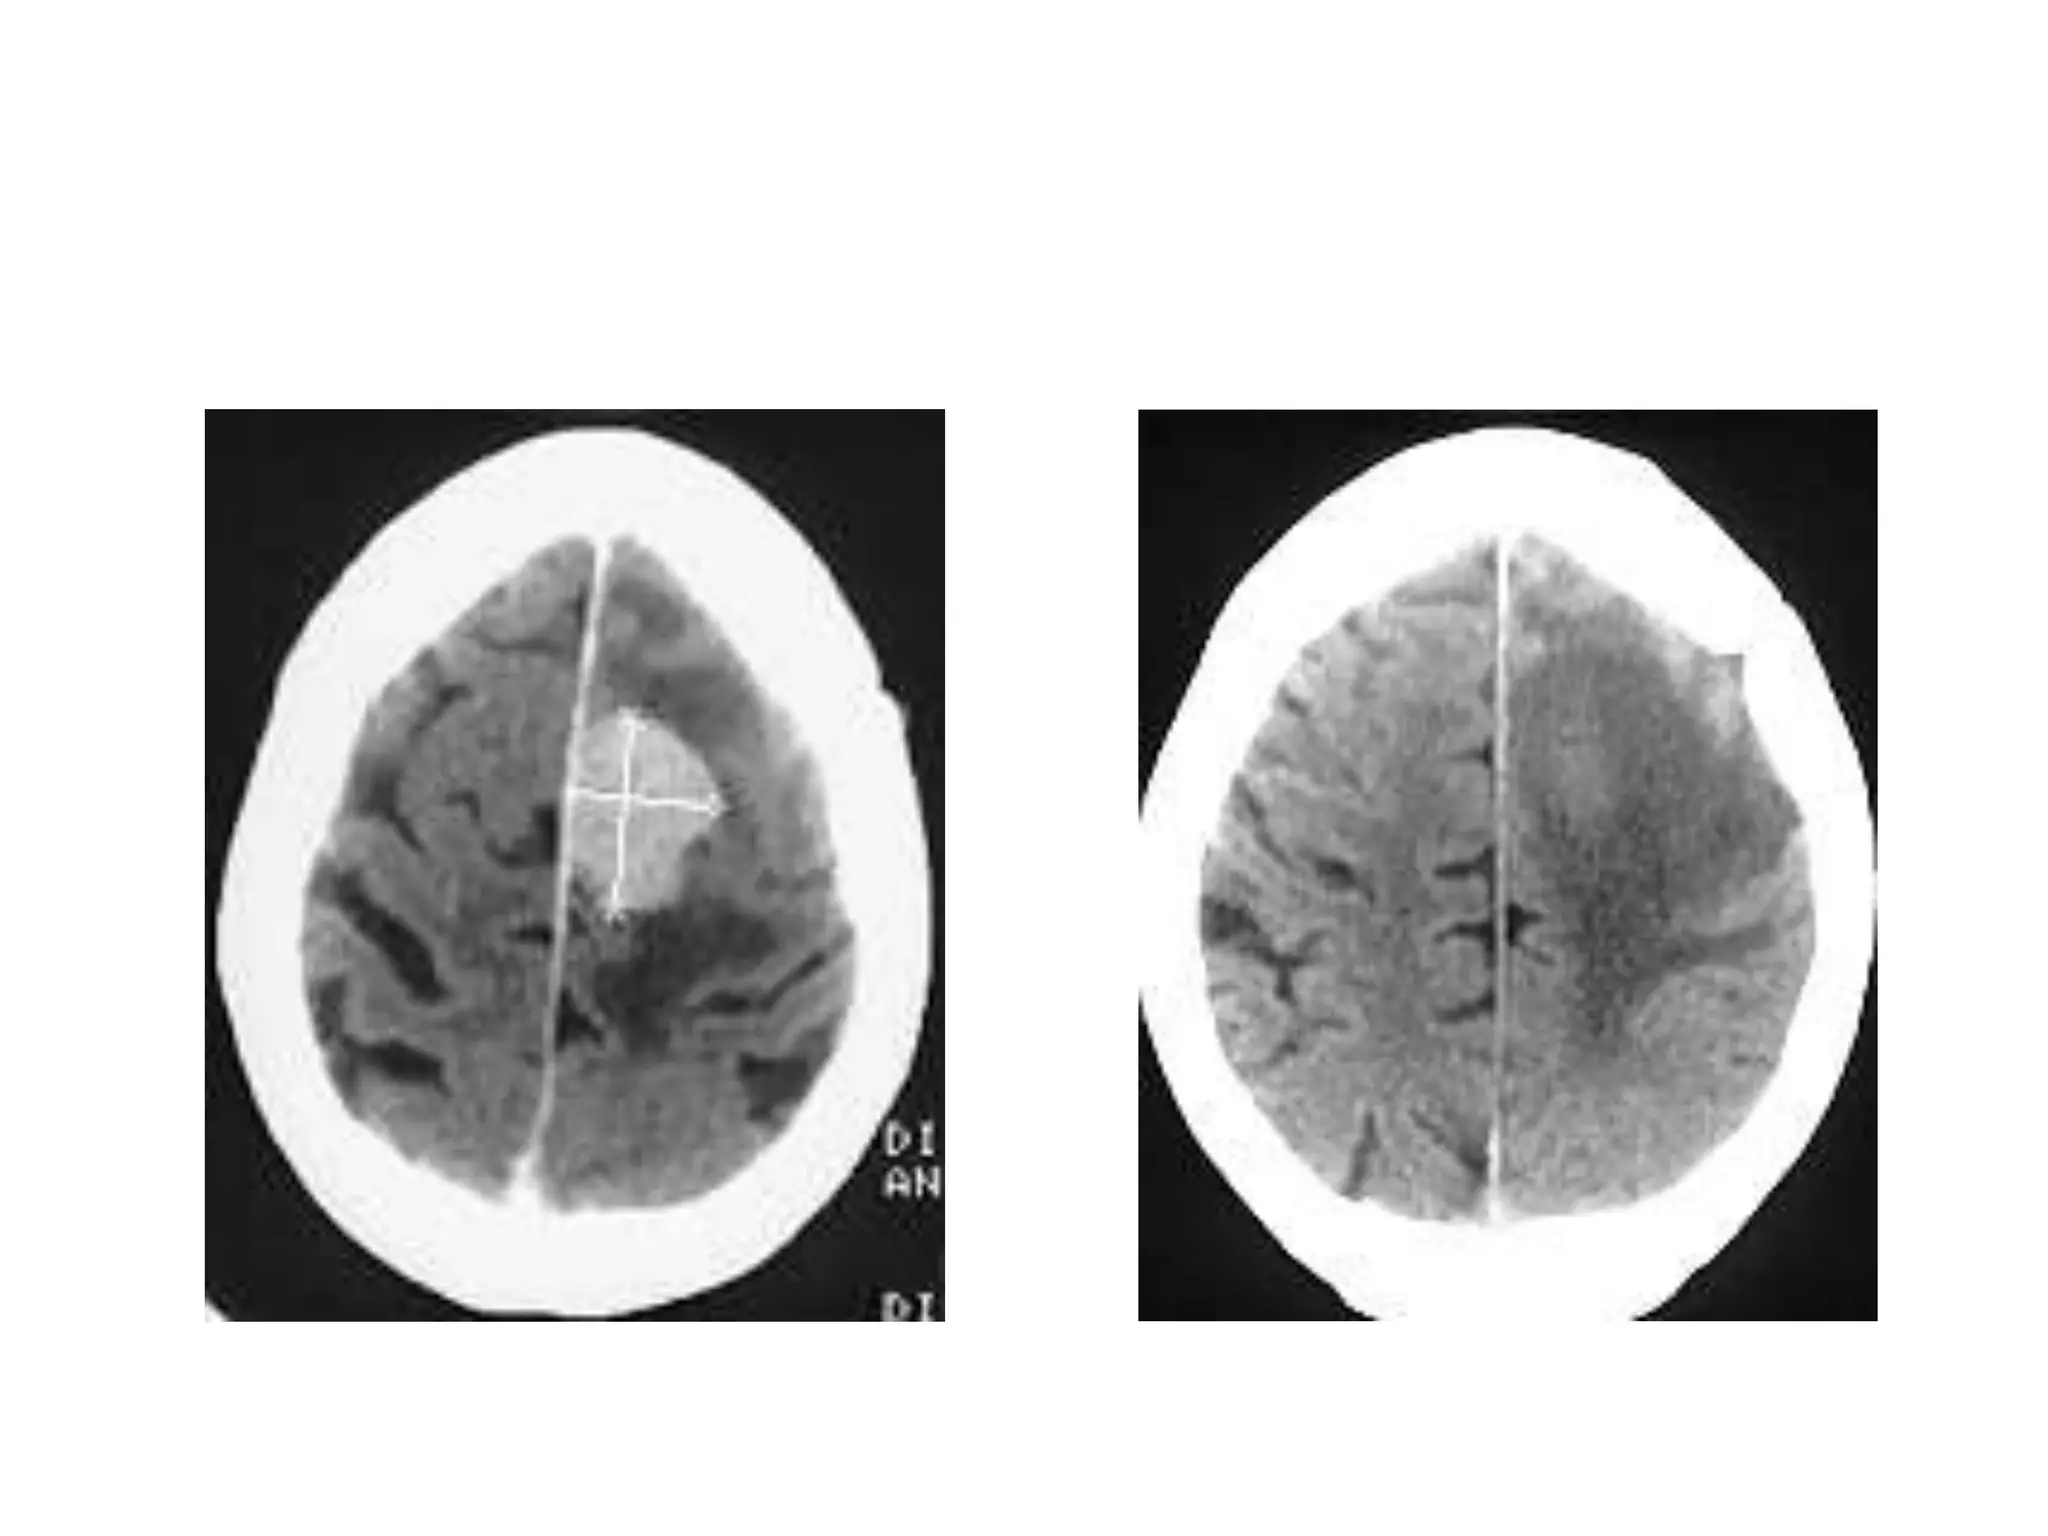

In cingulate or subfalcine herniation, the most

common type, the innermost part of the frontal

lobe is scraped under part of the falx cerebri, the

dura mater at the top of the head between the two

hemispheres of the brain.

Cingulate herniation can be caused when one

hemisphere swells and pushes the cingulate gyrus

by the falx cerebri.

This does not put as much pressure on the

brainstem as the other types of herniation, but it may

interfere with blood vessels in the frontal lobes that

are close to the site of injury (anterior cerebral

artery), or it may progress to central herniation.

Interference with the blood supply can cause

dangerous increases in ICP that can lead to more

dangerous forms of herniation.

Symptoms for cingulate herniation are not well

defined.Usually occurring in addition to uncal

herniation, cingulate herniation may present with

abnormal posturing and coma.

Cingulate herniation is frequently believed to be a

precursor to other types of herniation.

Central herniation

In central herniation, the diencephalon and parts of

the temporal lobes of both of the cerebral

hemispheres are squeezed through a notch in the

tentorium cerebelli.

Transtentorial herniation can occur when the brain

moves either up or down across the tentorium, called

ascending and descending transtentorial herniation

respectively; however descending herniation is much

more common.